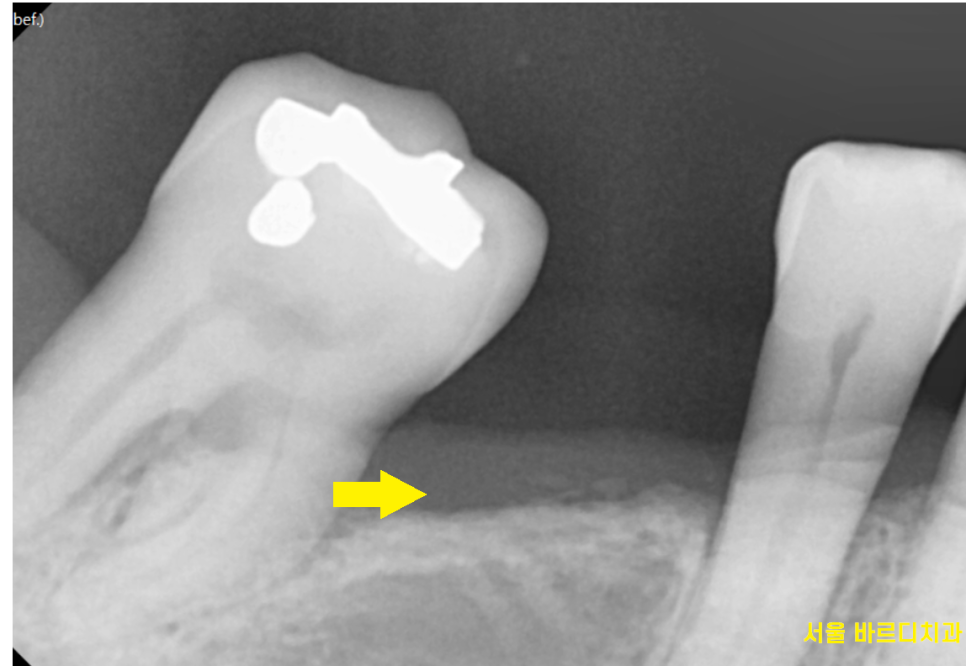

x-ray를 찍어보면

치아가 기울어진게 보이는데 말이죠

빠진 어금니 방치하다가

치아가 쓰러져

해당 환자분은 임플란트를 심을 공간이

부족하셨습니다.

환자분은 1개가 빠졌을 때

바로 치료받으셨으면

멀쩡한 옆에 어금니는 살릴 수 있었겠지만

너무 많이 쓰러져서..

고덕역 치과에서 뽑고 임플란트를 하셨습니다.